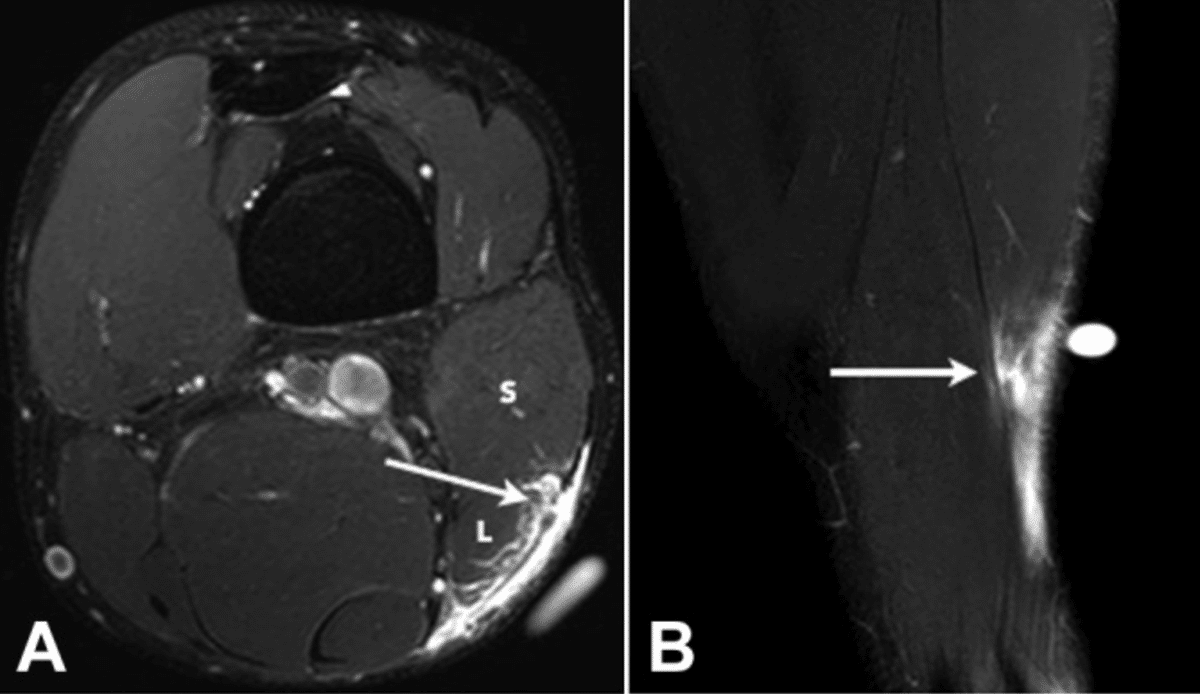

・Ⅱ型2度

(Pedret C, J Belg Soc Radiol. 2022から引用)

腱膜の連続性が背側部に途絶

(奥脇 透:大腿二頭筋肉ばなれの MRI 分類、臨床スポーツ、2019より引用)